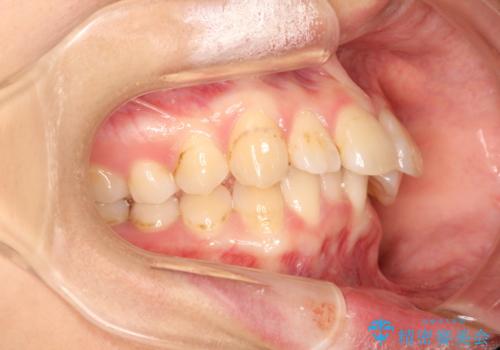

- 初診時には上顎前歯の突出、前歯部の深いかみ合わせ、叢生が見られる状態でした。

このケースでは非抜歯にて奥歯を後方に移動させる事で前歯の突出を改善するスペースを作り出していますが、これはマウスピースと顎間ゴムの併用によるもので、患者様のご協力の賜物と言えます。